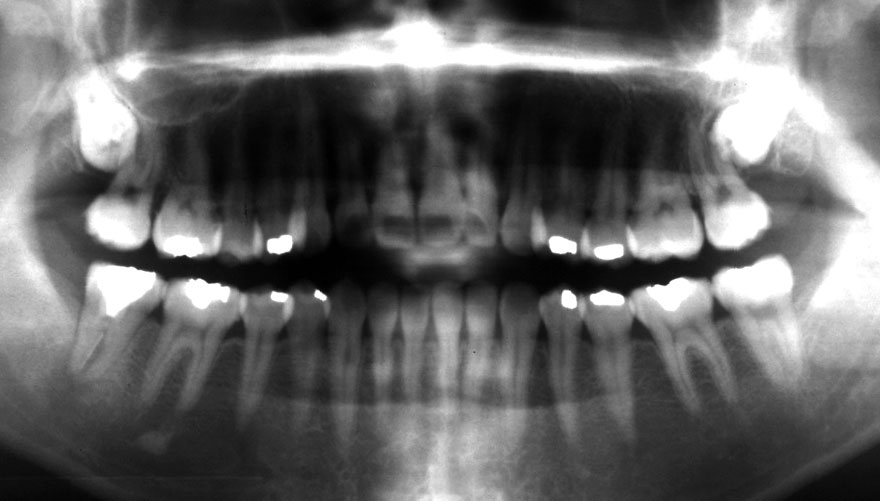

初診時 38歳 男性 平均歯槽骨喪失量:6.520mm

25年後 63歳

平均歯槽骨喪失量:8.57mm

25年間喪失量:-2.05mm

年間喪失速度:-0.08mm

(ケア頻度:1.38ヵ月ごと)